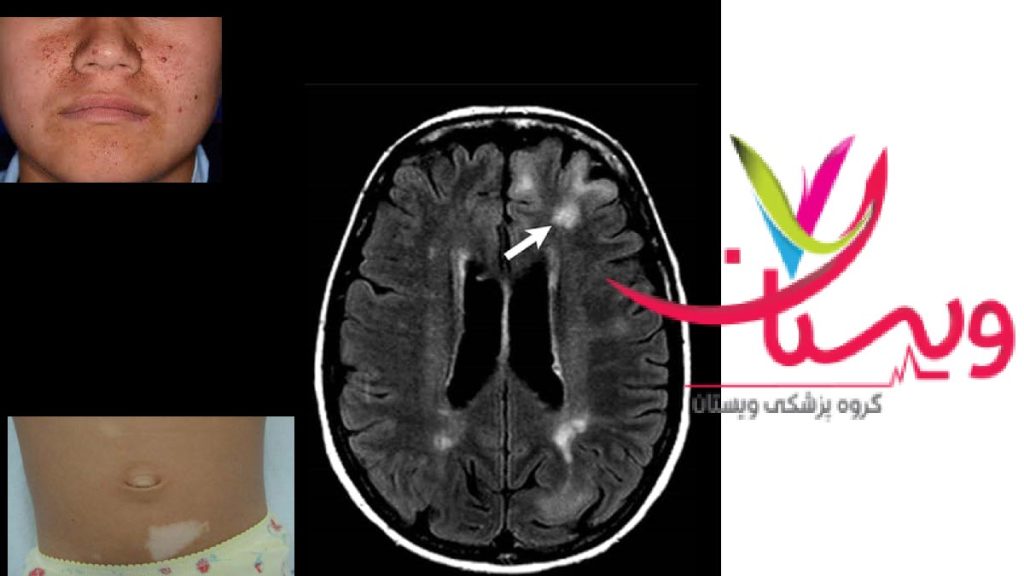

علائم بیماری توبروس اسکلروز میتواند در افراد متفاوت باشد و شدتهای مختلفی داشته باشد. این بیماری اغلب با لکههای سفید روی پوست، تومورهای کوچک روی صورت و رشد غیرطبیعی ناخنها شروع میشود.

لکههای سفید یا روشن روی پوست (hypomelanotic macules)

رشد تودههای کوچک و قرمز روی صورت به نام آدنوم سباسه

ناهنجاریهای ناخن و ایجاد فیبروما در اطراف آنها

| MRI مغز | شناسایی توبورهای مغزی و SEGA |

کاربر 2: این بیماران لکه های کلسیته در مغز دارند که با ام آر آی یا اسکن مشخص میشه و حملات تشنجی هم در بسیاری از بیماران وجود داره.

ضایعات پوستی توبروس اسکلروزیس

- لکههای سفید (Hypomelanotic Macules):

- از اولین و شایعترین نشانههابیماری پوستی اسکلروزیس هستند.

- معمولاً در بدو تولد یا اوایل کودکی ظاهر میشوند.

- شکل آنها ممکن است بیضی یا برگمانند باشد.

- آنگیوفیبروما (Angiofibroma):

- برجستگیهای کوچک صورتی یا قرمز که معمولاً در ناحیه گونهها و بینی دیده میشوند.

- در دوران کودکی یا نوجوانی بروز میکنند و با افزایش سن، تعداد و اندازه آنها ممکن است بیشتر شود.

- ضایعات ناخنی (Periungual Fibromas):

- تومورهای کوچکی هستند که در اطراف یا زیر ناخنها شکل میگیرند.

- ممکن است دردناک باشند و روی عملکرد انگشتان تأثیر بگذارند.

- لکههای زبر و ضخیم پوست (Shagreen Patches):

- معمولاً در ناحیه کمر یا پایین کمر ظاهر میشوند.

- سطحی زبر و چرممانند دارند و رنگ آنها ممکن است کمی تیرهتر از پوست طبیعی باشد.